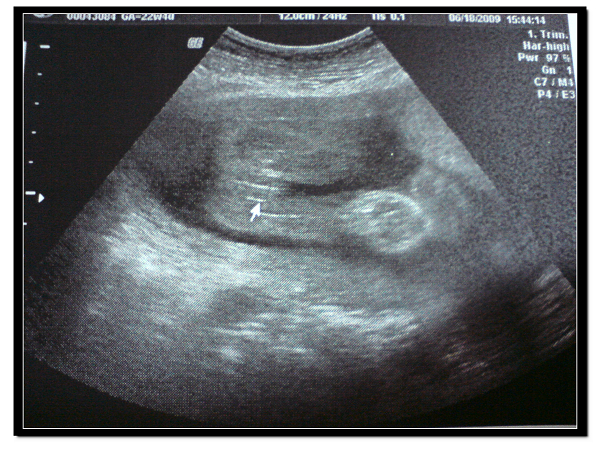

早在幾個星期前就預約了高層次超音波,聽說這種超音波可以特別針對baby的五臟六腑作檢查

像是大腦、小腦、心臟、肝、腎等等~

醫生開始檢查,其實比較明顯的器官我大概都看得出來

不過像是肝、腎等等的,我真的無法辨識,只能說醫生真的是經驗豐富~ = ="

baby的重量是580g,100個baby中,從最重排下來,是第54名,還不賴啦

而且這次的檢查也確定了我的BABY是女生~~~女生~~~ :D